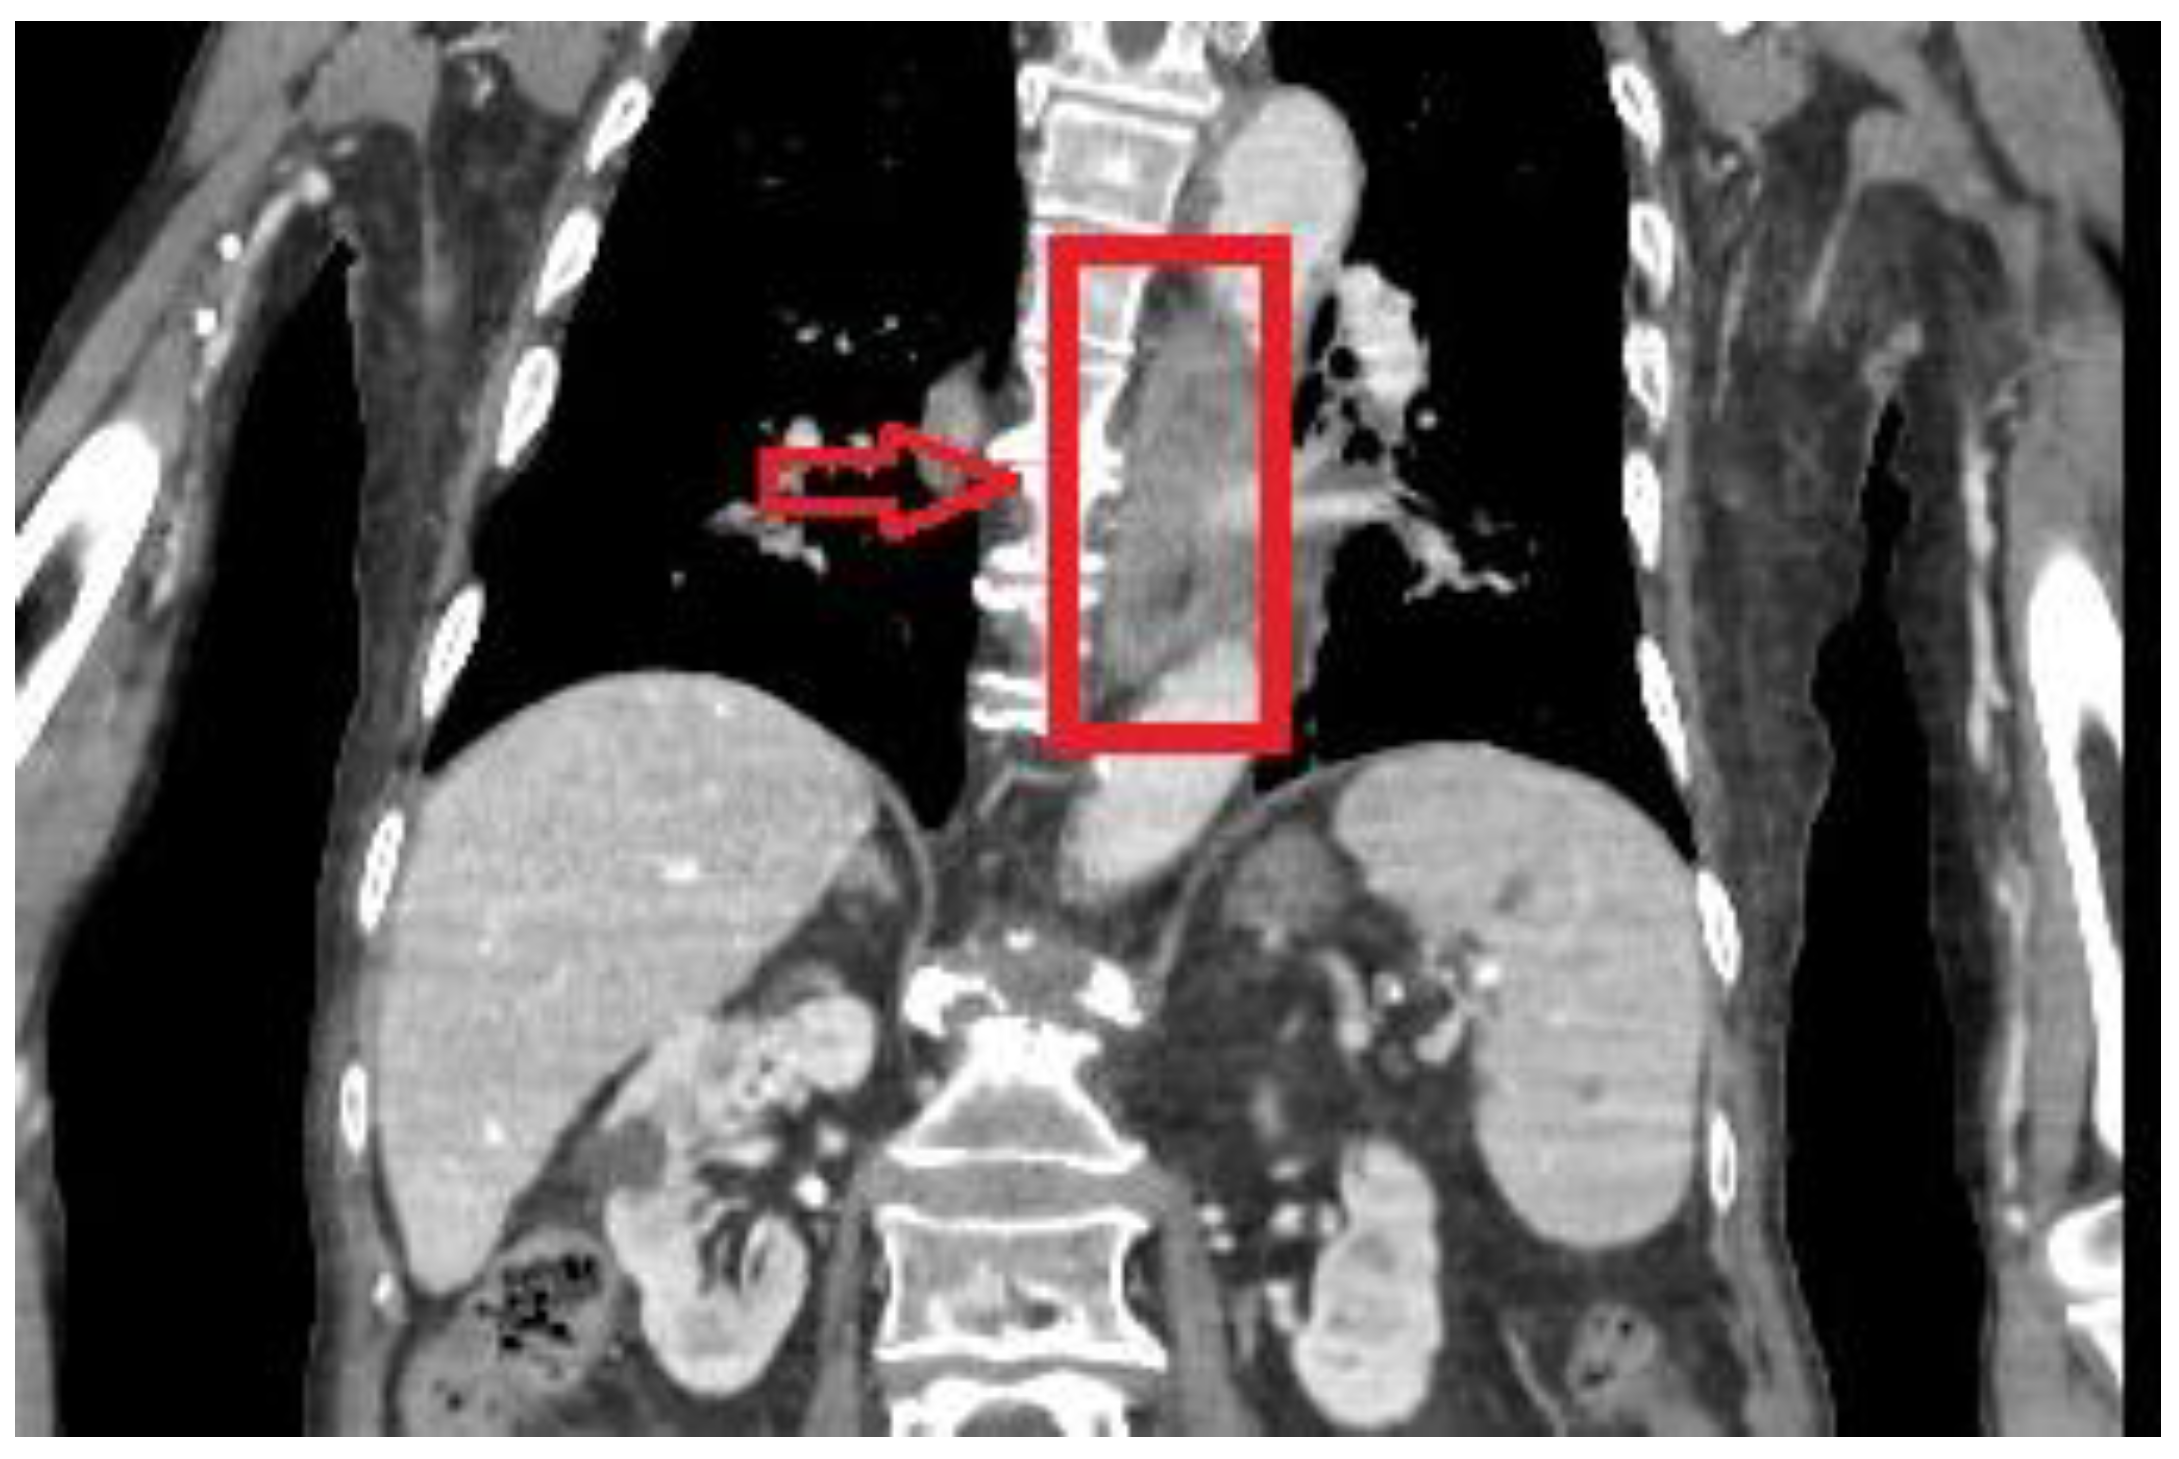

While in the emergency department, a thoraco-abdominal computer tomography (CT) scan was performed and revealed diffuse parieto-mucosal thickening of the medium-distal tract of the esophagus with edematous imbibition of the mediastinal adipose tissue (Figure 1). Celiac tripod as well as superior mesenteric artery were patent. Due to imaging findings and clinical presentation, neoplastic degeneration or an inflammatory process were mainly included in the differential diagnosis.

Figure 1.

Computed tomography showing perieto-mucosal thickening of the medium–distal tract of the esophagus.